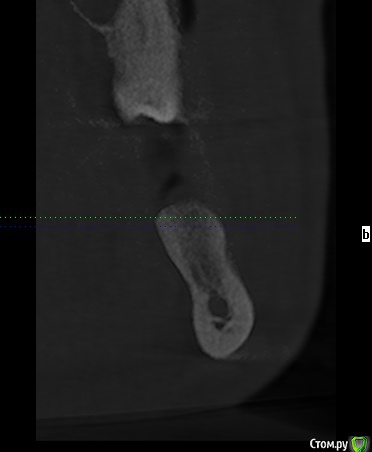

erm Опубликовано 2 февраля, 2016 Автор Поделиться Опубликовано 2 февраля, 2016 во еще снимок из клкт Ссылка на комментарий

erm Опубликовано 2 февраля, 2016 Автор Поделиться Опубликовано 2 февраля, 2016 попробуйте выложить срезы КТ той области, где удаляли зубвот не знаю оно или нет Ссылка на комментарий

carloss Опубликовано 2 февраля, 2016 Поделиться Опубликовано 2 февраля, 2016 (изменено) по этим срезам вроде все нормально.. попробуйте еще несколько таких же, чуть спереди и сзади.. пытаюсь скачать вашу КТ, не получается у меня открыть Изменено 2 февраля, 2016 пользователем carloss Ссылка на комментарий